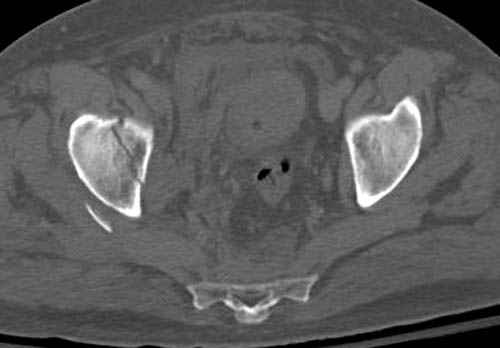

Дополнительно имеется перелом ацетабулума: задняя

колонна с полупоперечным переломом, и переломы костей лица.

На седьмой день зафиксирован перелом ацетабулума через задний доступ. Перед операцией для профилактики DVT, IVC фильтер, также получает Lovenox.

Отправитель: Evgueny Tchekashkine 30 Ноябрь 2007, 16:57

|

Джолдас,

По возможности вышлите снимки, сканы таза до реконструкции, интраоперационные.

По снимку создается впечатление о высоком поперечном переломе, задней колонны, стенки; почему не пользовались *magic screw*?

Положение больного на животе или на боку?

Кава фильтр при переломах таза - это протокол или только для пациентов с политравмой?

Фиксация таза до реконтструкции с момента поступления? Когда начали DVT профилактику: сразу при поступлении или накануне реконструкции?